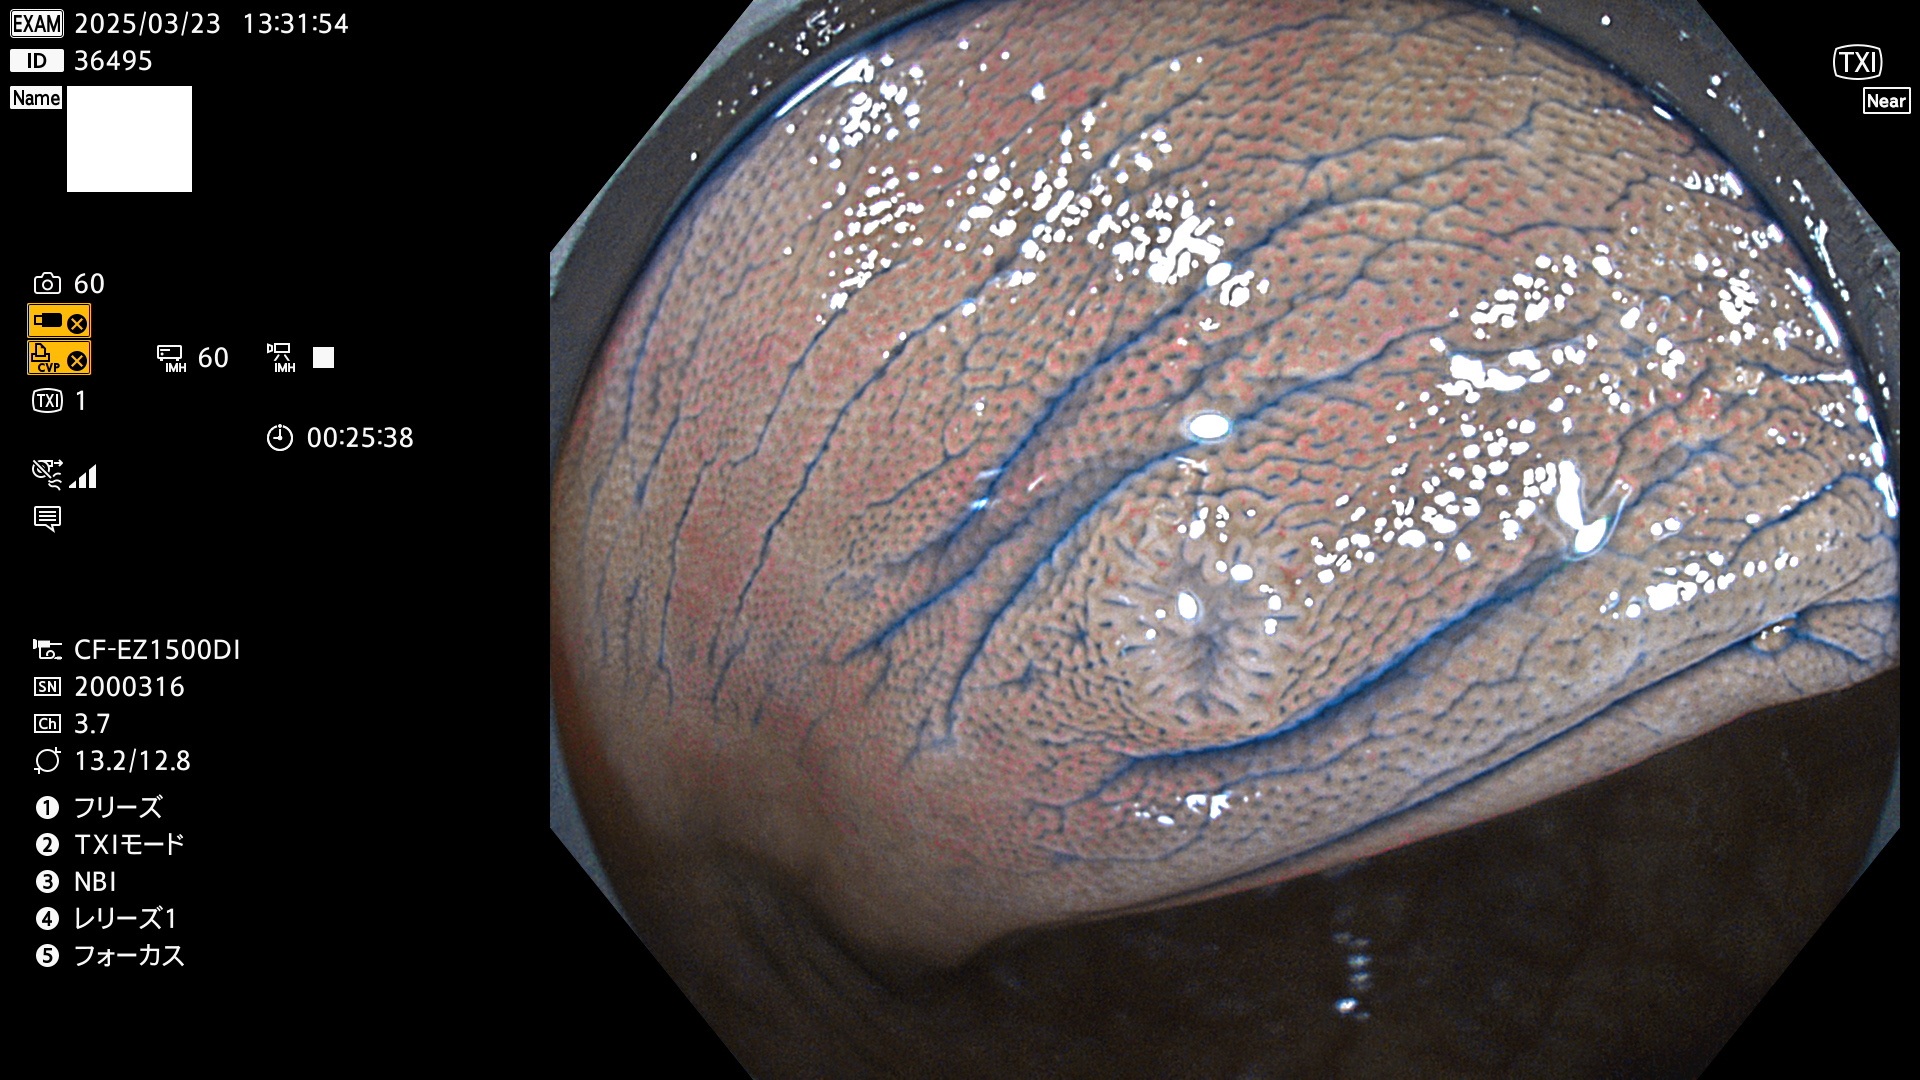

今週のUb、Uc型腺腫

完全に平坦な物をUb、陥凹している物をUcと呼びます。Ubは認識が困難で、Ucはびらん(炎症)と紛らわしいために見落とされやすく、「内視鏡後・大腸癌」の原因になります。

毎週の検査(木・金・土・日)に発見されたUb、Uc型・腺腫を、その週の日曜の夜にUPし1週間、提示します。

抽出の対象期間 2025年3月20日〜3月23日の4日間(48件の検査)10個 (10/48=21%)